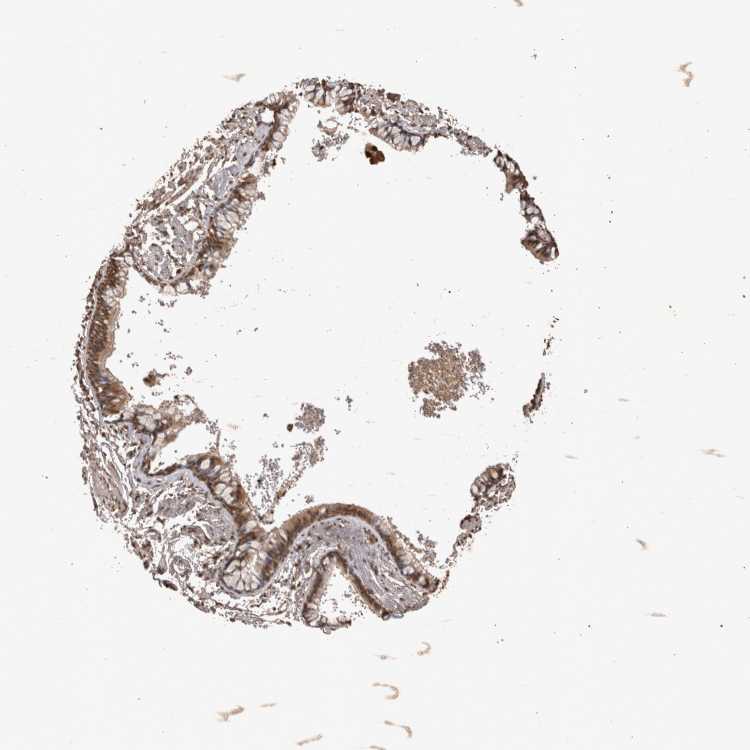

SOFT TISSUE 1 - Antibody stainingi

Antibody staining in the annotated cell types in the current human tissue is reported as not detected, low, medium, or high, based on conventional immunohistochemistry profiling in selected tissues. This score is based on the combination of the staining intensity and fraction of stained cells.

Each image is clickable and will lead to virtual microscopy that enables deeper exploration of all samples and also displays staining intensity scores, fraction scores and subcellular localization as well as patient and tissue information for each sample.

Antibody CAB024984

Fibroblasts High

SOFT TISSUE 2 - Antibody stainingi

Chondrocytes High

Peripheral nerve High